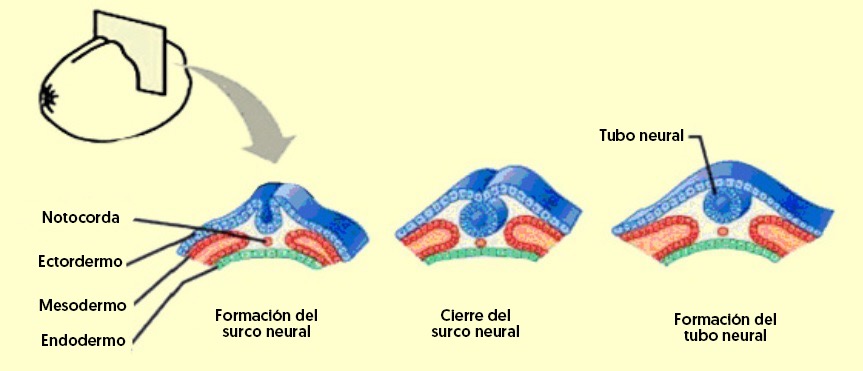

Tras la fecundación del óvulo se inicia la formación del cigoto que se implanta en el útero. En este momento comienza el proceso de gastrulación, en el que empiezan a diferenciarse los distintos tipos de células. Un proceso que hace que el cigoto se convierta en una gástrula, que presenta tres capas de células claramente diferenciadas:

La primera es el mesodermo, donde se originan los huesos y la masa muscular. La segunda es el endodermo, desde donde se forma el páncreas, el esófago y el estómago. Por último, tenemos el ectodermo, donde nacen las estructuras del sistema nervioso, así se inicia la formación cerebral.

A las dos semanas de la concepción comienza el proceso de desarrollo del cerebro. En este caso, el ectodermo sufre algunos cambios estructurales y se inicia la formación de la placa neural. Para el día dieciocho del embarazo, en la placa comienza el proceso de neurulación. En este proceso, los extremos de dicha placa neural se comienzan a elevar hacia la línea media y, después, forman un surco. Por dicho surco se desarrollan dos líneas, las cuales se fusionan y constituyen el tubo neural.

Este tubo comienza un proceso de sellado que inicia en la parte media, sigue a la parte anterior y, por último, a la zona posterior. Asimismo, empieza la formación de la cresta neural, importante para el desarrollo del sistema nervioso. Finalmente, el proceso culmina aproximadamente el día veintiséis o veintiocho del embarazo. Si se presenta algún daño en tal proceso, se pueden generar enfermedades como la espina bífida o el encefalocele.